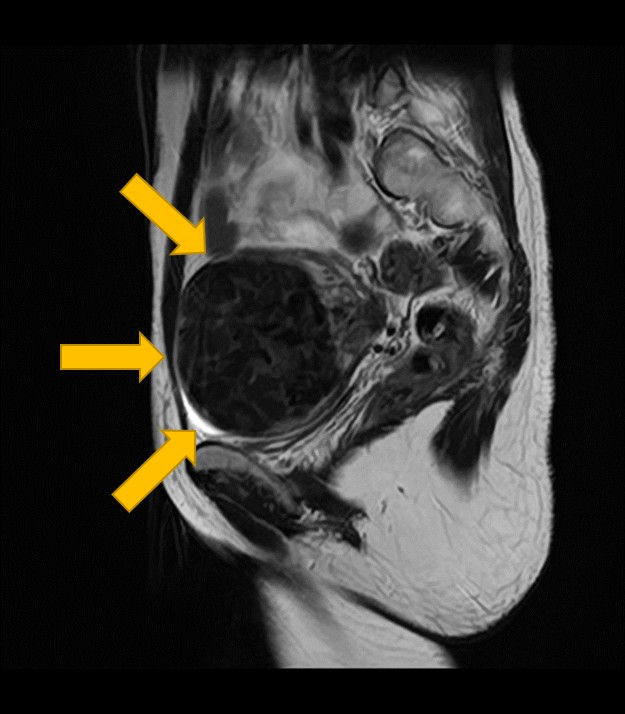

子宮筋腫の数、大きさ、正確な位置、子宮の筋肉(筋層)との関係、さらには筋腫の種類(粘膜下筋腫、筋層内筋腫、漿膜下筋腫など)を詳しく評価します。

手術が必要な場合の術前情報として不可欠なだけでなく、子宮肉腫など悪性腫瘍との鑑別にも役立ちます。

2. 卵巣腫瘍(嚢腫)のMRI:良性・悪性を判断する「中身」と「充実部分」の評価

卵巣嚢腫の中身が液体、脂肪、血液など何であるか、嚢腫壁の性状(肥厚、隔壁の有無)、充実部分の有無や血流を評価することで、良性か悪性(がん)かの可能性を判断する重要な手がかりとなります。